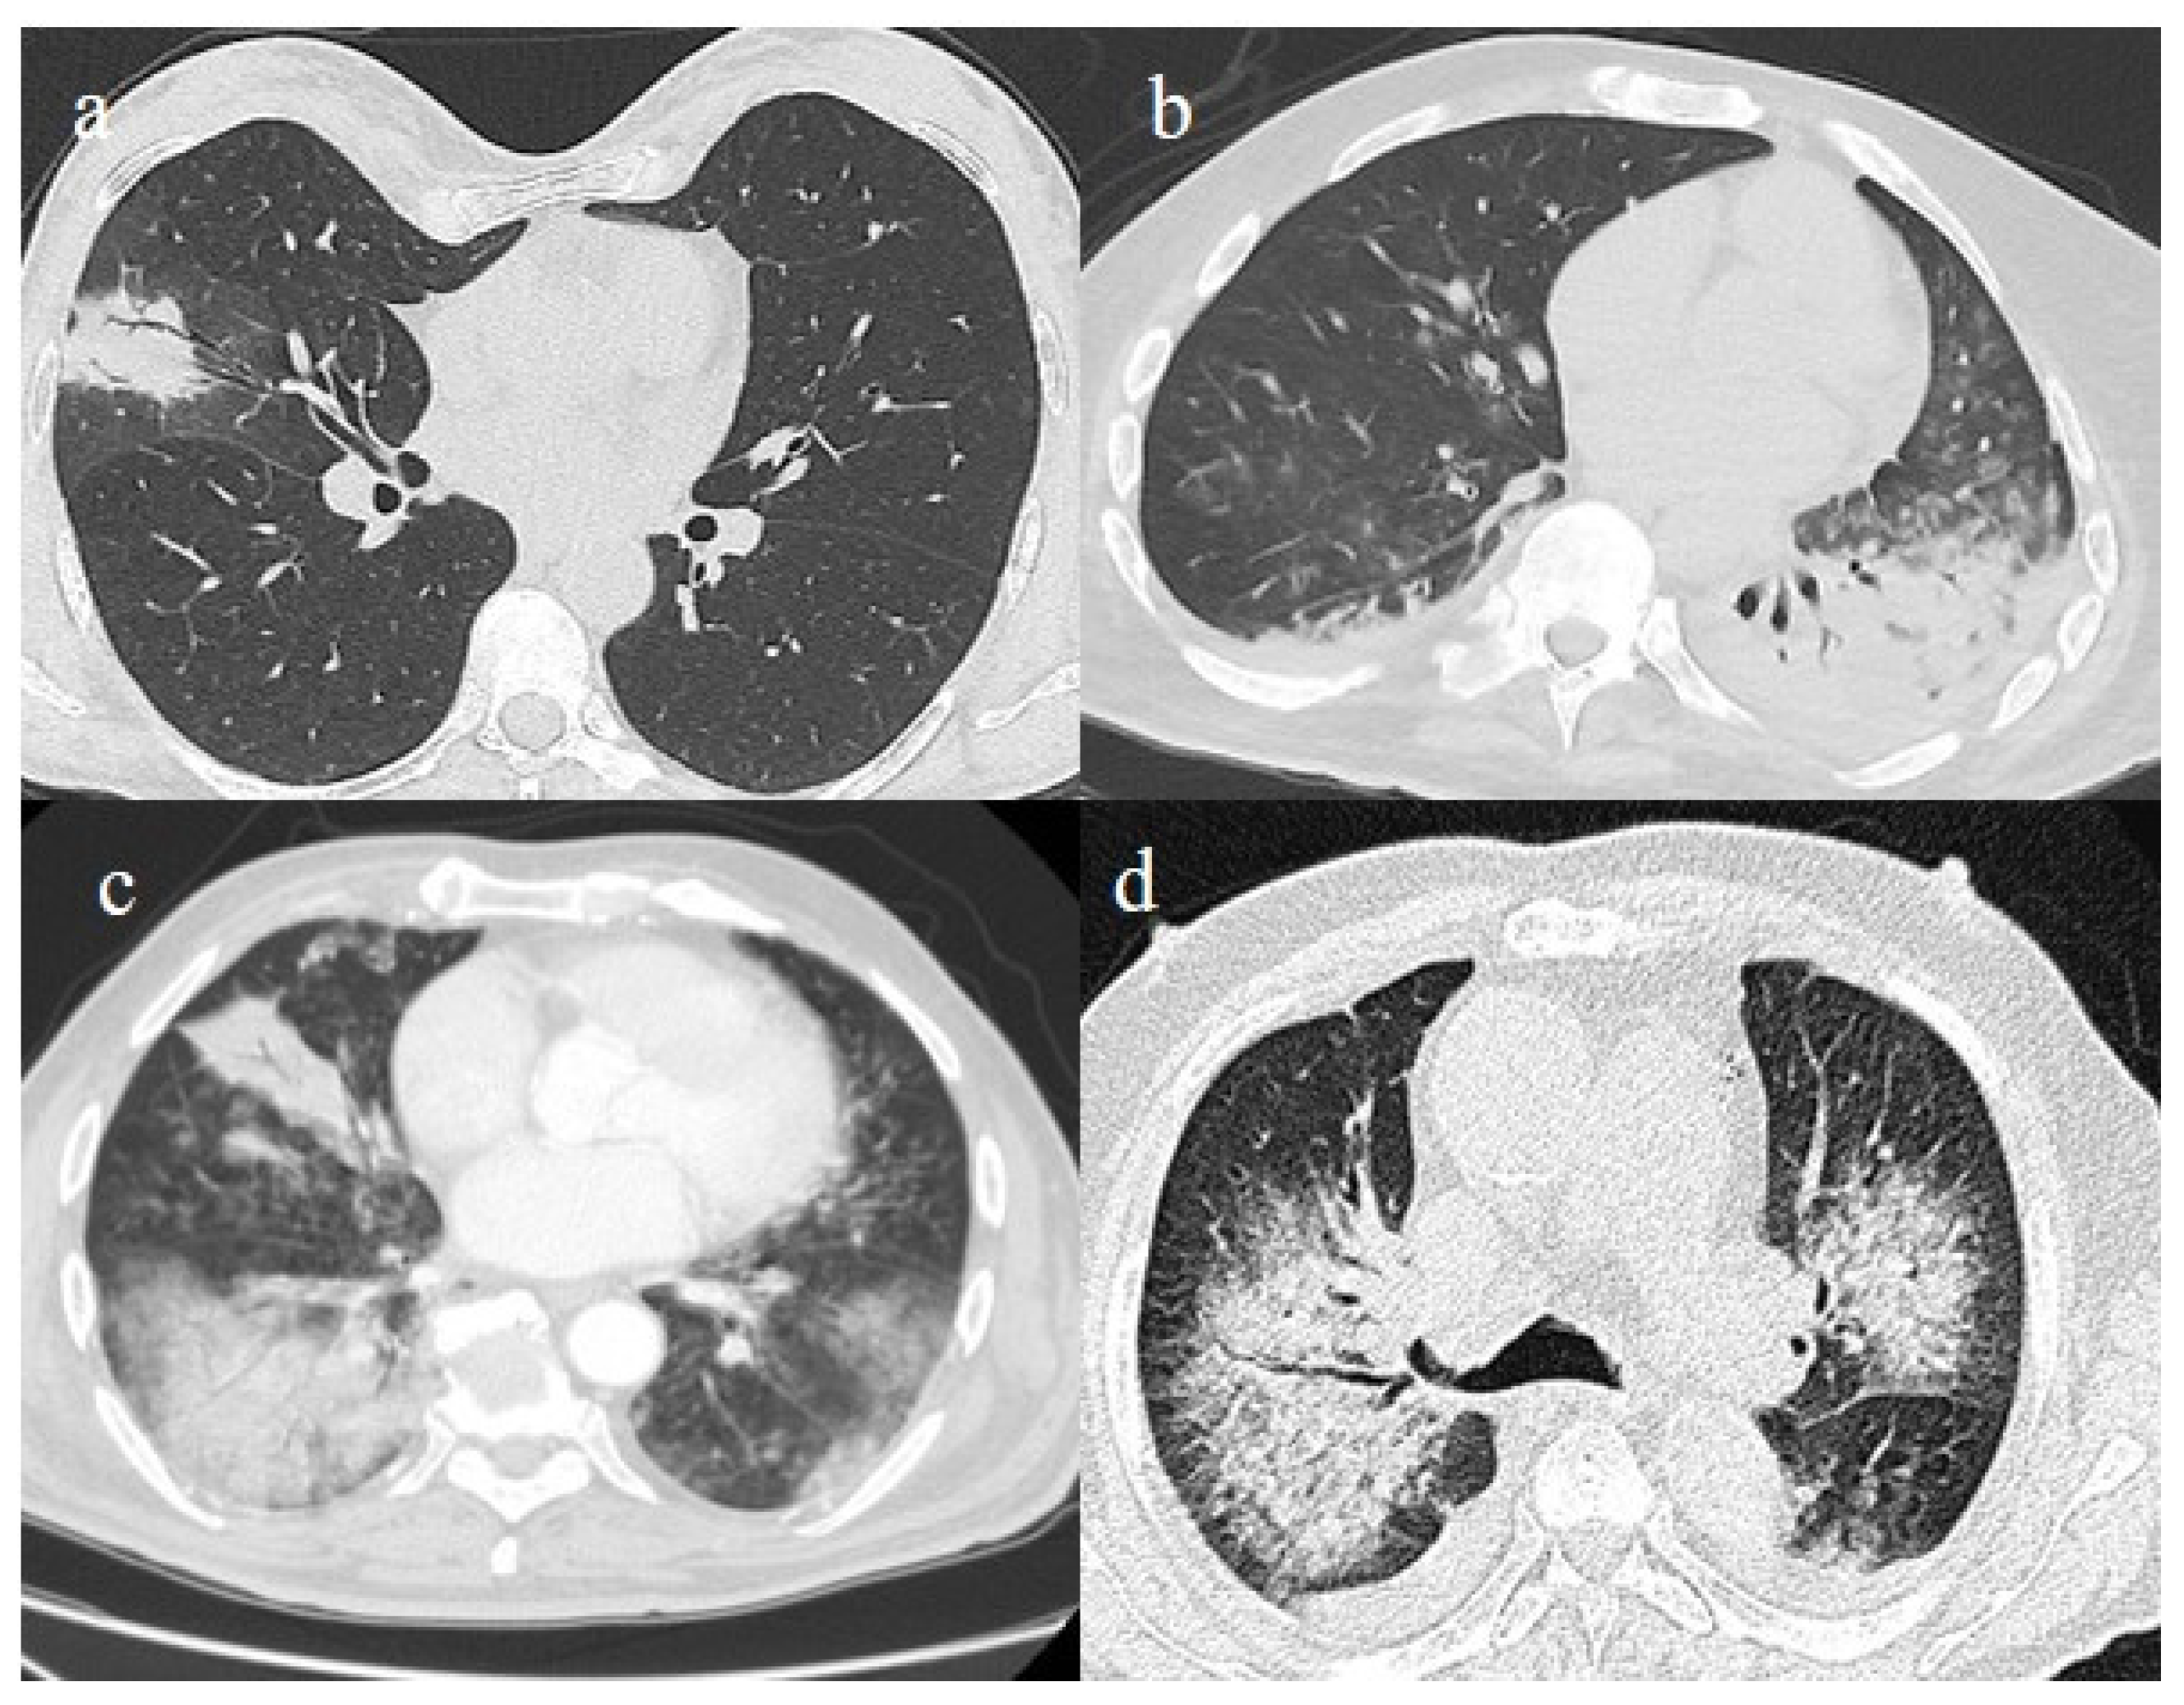

3.3.1. Acute Respiratory Distress Syndrome

- Schultz, M.J.; van Meenen, D.M.; Bos, L.D. COVID-19-related acute respiratory distress syndrome: Lessons learned during the pandemic. Lancet Respir. Med. 2022, 10, 1108–1110. [Google Scholar] [CrossRef]

- Aslan, A.; Aslan, C.; Zolbanin, N.M.; Jafari, R. Acute respiratory distress syndrome in COVID-19: Possible mechanisms and therapeutic management. Pneumonia 2021, 13, 1–15. [Google Scholar] [CrossRef]

- Lu, S.; Huang, X.; Liu, R.; Lan, Y.; Lei, Y.; Zeng, F.; Tang, X.; He, H. Comparison of COVID-19 Induced Respiratory Failure and Typical ARDS: Similarities and Differences. Front. Med. 2022, 9, 829771. [Google Scholar] [CrossRef]

- Pfortmueller, C.A.; Spinetti, T.; Urman, R.D.; Luedi, M.M.; Schefold, J.C. COVID-19-associated acute respiratory distress syndrome (CARDS): Current knowledge on pathophysiology and ICU treatment—A narrative review. Best Pract. Res. Clin. Anaesthesiol. 2020, 35, 351–368. [Google Scholar] [CrossRef]

- Gosangi, B.; Rubinowitz, A.N.; Irugu, D.; Gange, C.; Bader, A.; Cortopassi, I. COVID-19 ARDS: A review of imaging features and overview of mechanical ventilation and its complications. Emerg. Radiol. 2022, 29, 23–34, Erratum in Emerg. Radiol. 2022, 29, 225. [Google Scholar] [CrossRef]